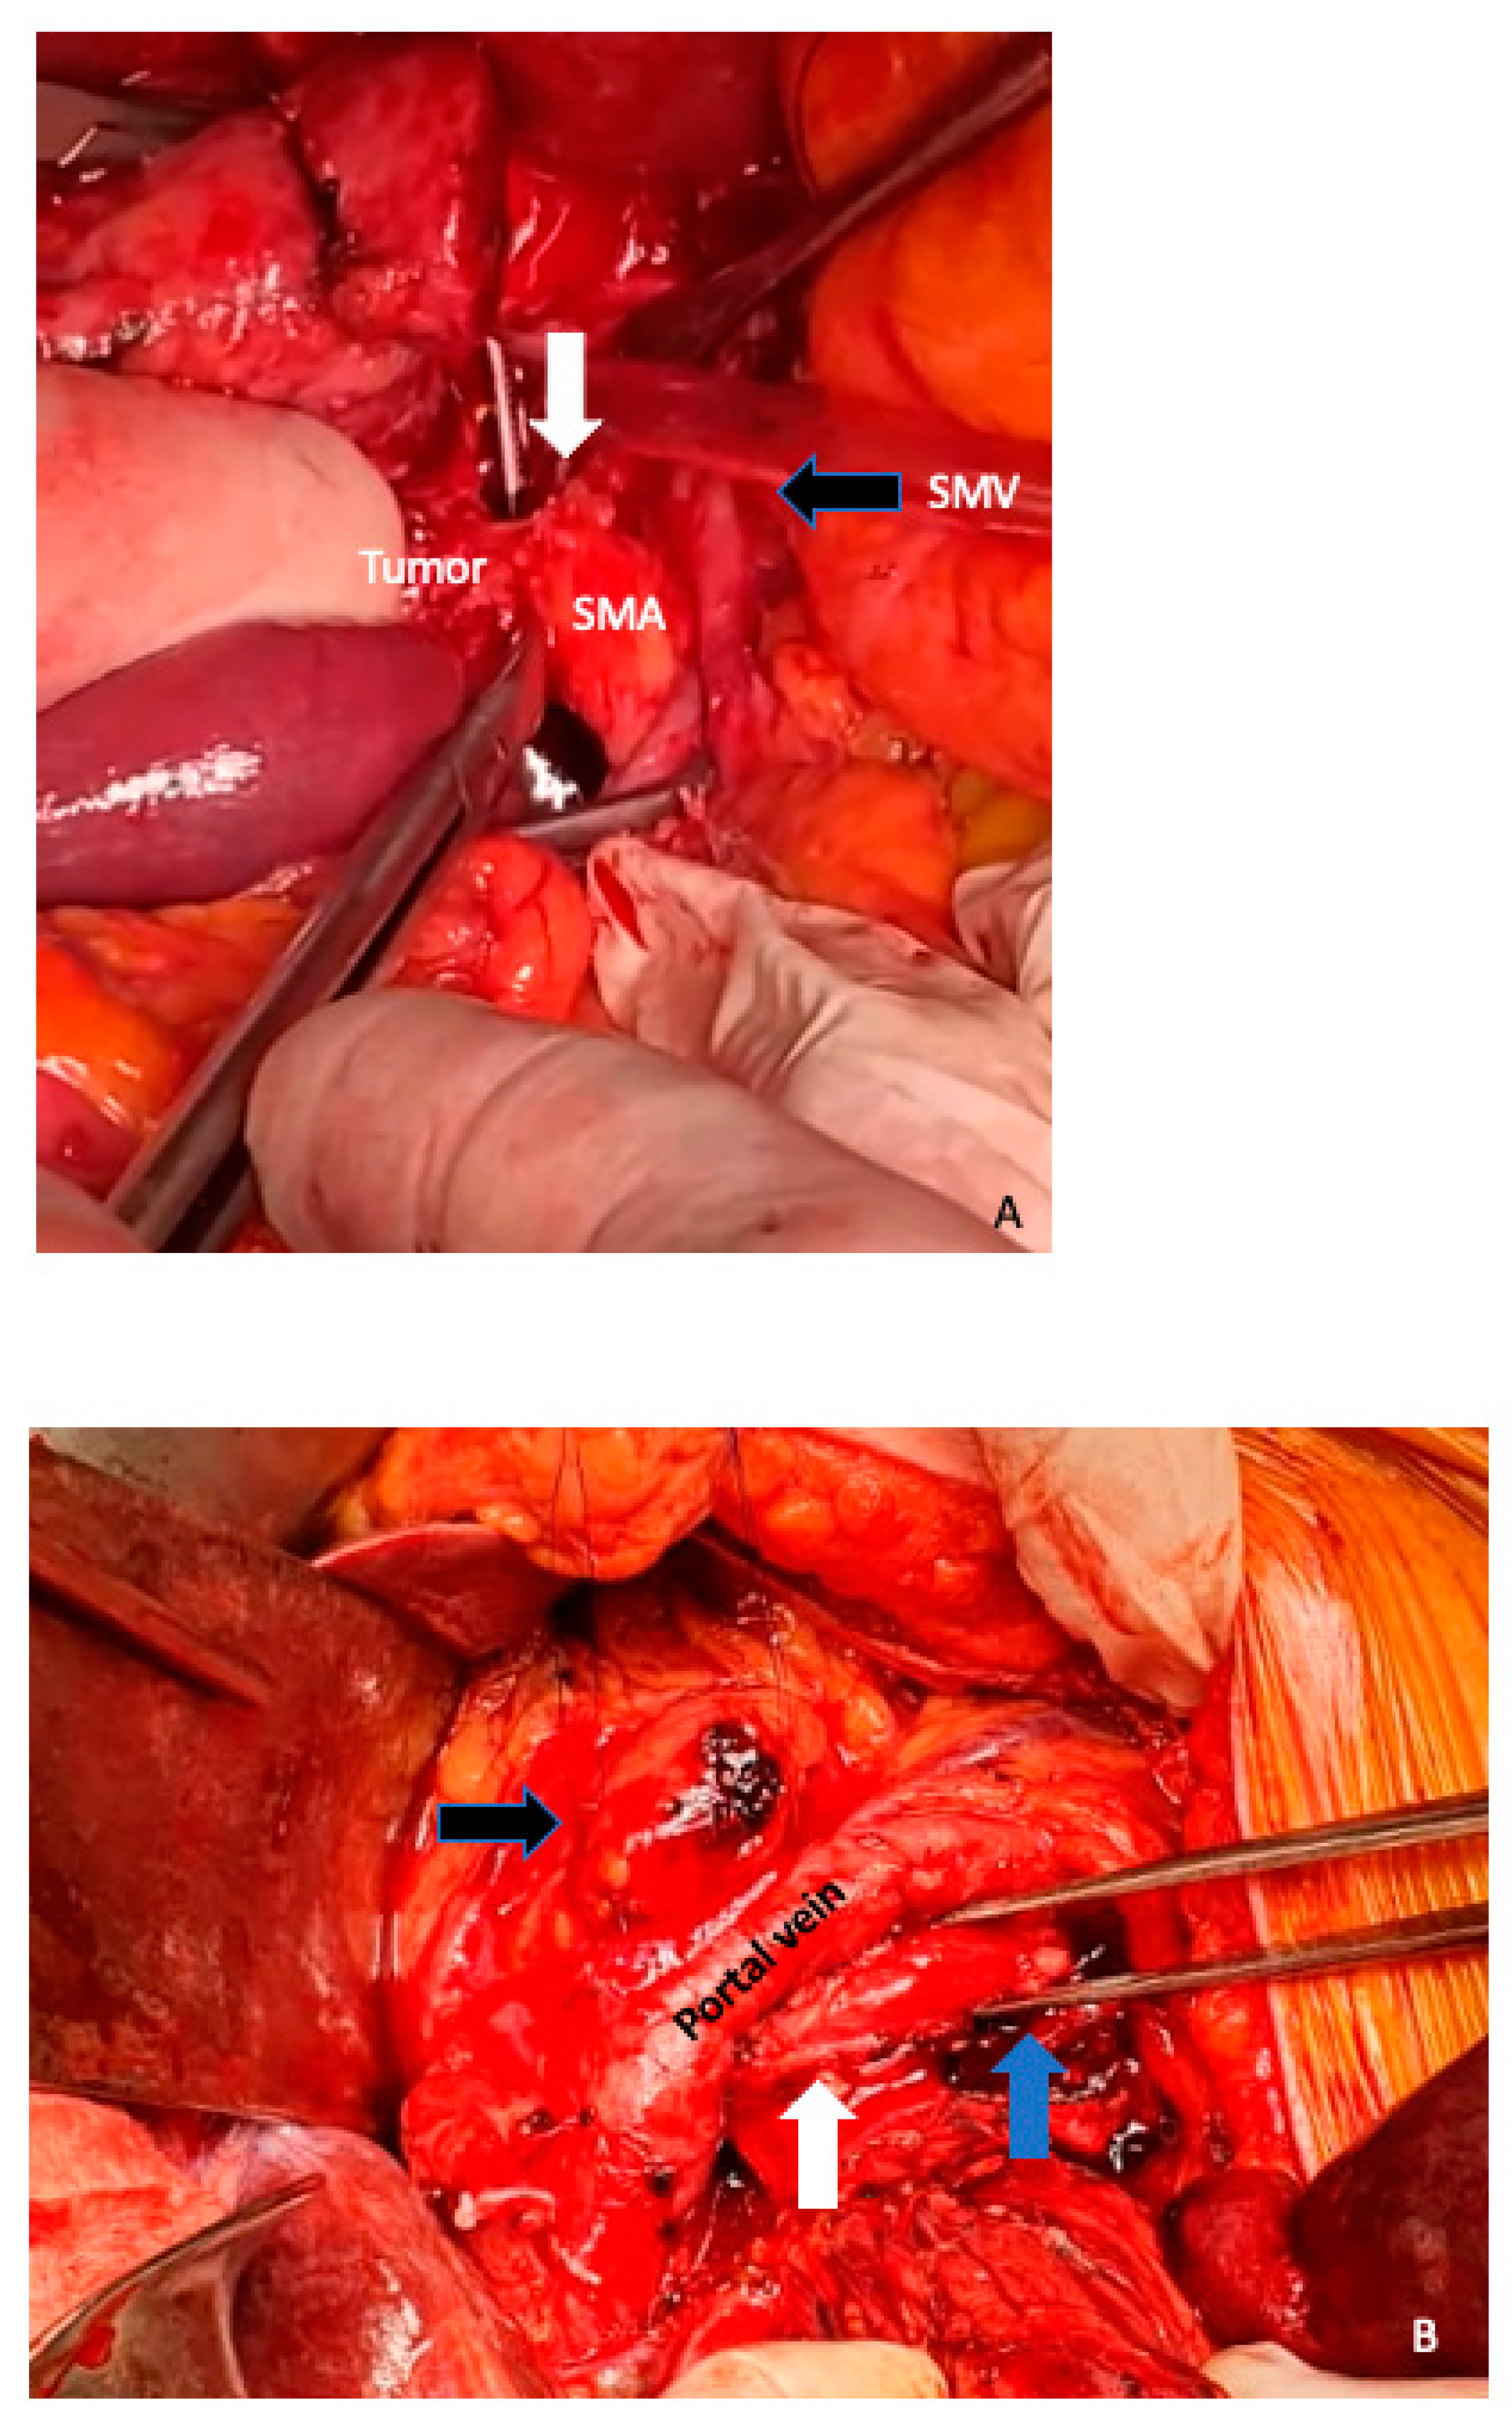

3. Surgical Aspects

6. Arterial Resection